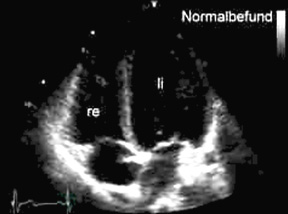

Echokardiographie (Vierkammerblick): Normalerweise sind die linke Herzkammer (rechts oben) und der Herzvorhof (rechts unten) größer als rechtsseitigen Herzhöhlen.  Beim Cor pulmonale sind die Größenverhältnisse aufgrund des erhöhten Drucks im rechten Herz seitenvertauscht.